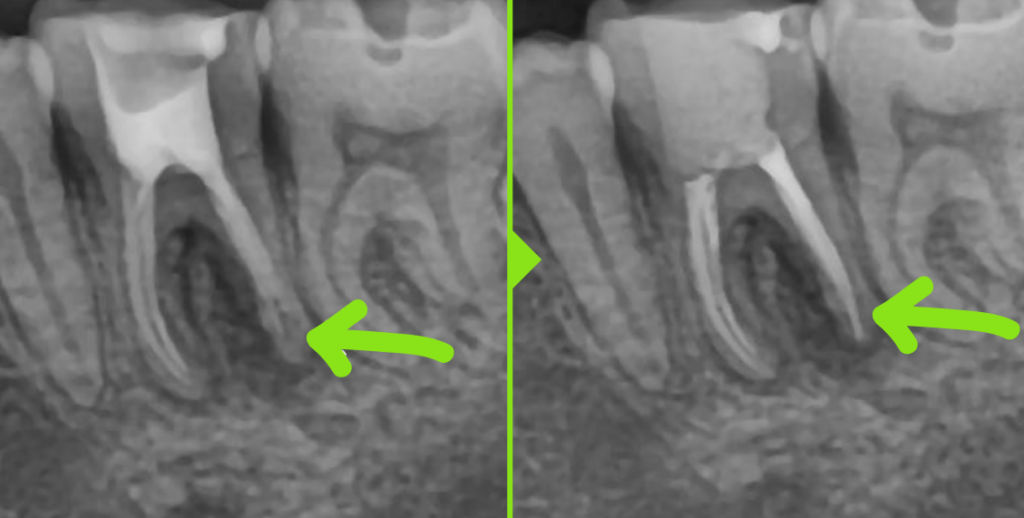

타 치과에서 재신경치료를 진행했으나

실패하여 내원한 케이스입니다.

본원에서 재신경치료로

내원하신 당일 치료를 마무리했으며,

6개월 후 검사에서 염증 범위가 크게 감소하고

통증도 사라진 상태가 확인되었습니다.